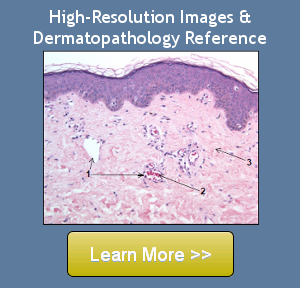

Histologic Features

- Closely-set spongiotic vesicles containing many eosinophils and mononuclear cells

- Many dyskeratotic keratinocytes and exocytosis of eosinophils

- Edema of papillary dermis

- Scattered eosinophils and lymphocytes in the upper dermis

- A superficial perivascular infiltrate containing lymphocytes and eosinophils